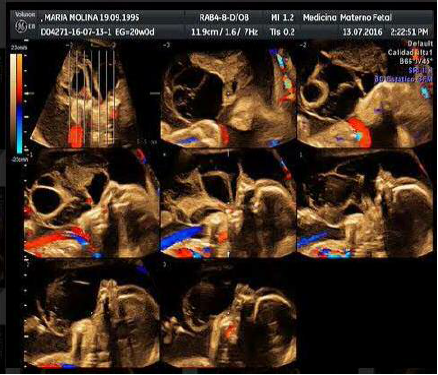

Paciente de 20 años de edad, procedente del estado Carabobo, de ocupación asistente administrativo, primigesta, con embarazo de 21 semanas, quien acude a la unidad de perinatología del Hospital materno-infantil “Dr. José María Vargas” para evaluación morfogenética del segundo trimestre. Sin antecedentes familiares y personales pertinentes, con un solo control prenatal para el momento de la evaluación. Se realizan estudios de laboratorio de rutina prenatal sin alteraciones y el cariotipo reporta feto 46 XY normal. El estudio ecográfico perinatal revela embarazo de 21 semanas con feto único, longitudinal, podálico, posición derecha anterior con imagen que emerge de cavidad bucal con aspecto ecomixto, lobulado (fig. 1, 2, 3) y polihidramnios con índice de líquido amniótico ILA P>95, planteándose como diagnósticos aparte de encefalocele anterior, épulis, epignatos, hamartomas entre otros tumores que protruyen a través de la cavidad oral. Resto del examen sin alteraciones. La finalización del embarazo se realiza por vía vaginal en la misma semana. En la autopsia perinatal se evidencia gran masa oral (fig. 4 y 5), con un componente quístico y sólido secundario debido al conducto esfenoideoccipital persistente. El contenido del encefalocele basal además de meninges y líquido cefalorraquídeo fue el lóbulo occipital, parte del tronco encefálico y la glándula pituitaria (fig. 6).